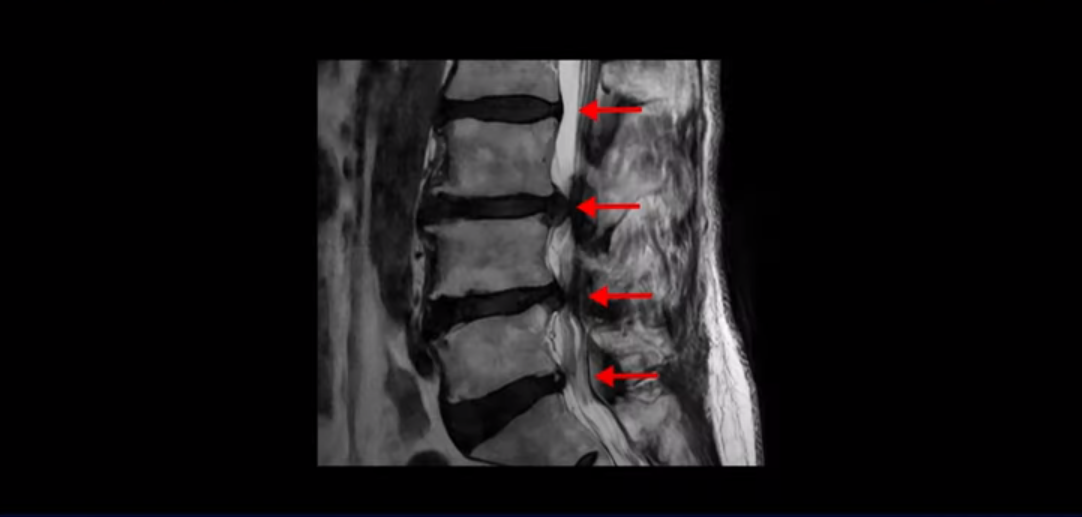

이분은 허리부터 다리, 복숭아뼈까지 극심하게 저리고 아픈 분입니다. MRI를 보시면 허리 4마디가 안 좋습니다.

그중에서도 3번 4번과 4번 5번 마디가 가장 안 좋습니다. 보시다시피 두 마디에 심한 중심성 협착이 있습니다.

이렇게 허리에서 신경이 눌리니까 다리가 저리고 종아리가 터질 듯이 아픕니다. 그래서 걷지를 못하고 가다 쉬고 가다 쉬고 그런 겁니다. 그런데 이런 분들이 수술 없이 치료가 가능한 이유는 근육재활치료와 운동으로 근육이 좋아지면 허리를 더 잘 지탱해 주니까 신경이 덜 눌리게 되는 겁니다. 모든 협착증 환자는 신경 구멍도 좁아져 있지만 근육도 다 망가져 있습니다.